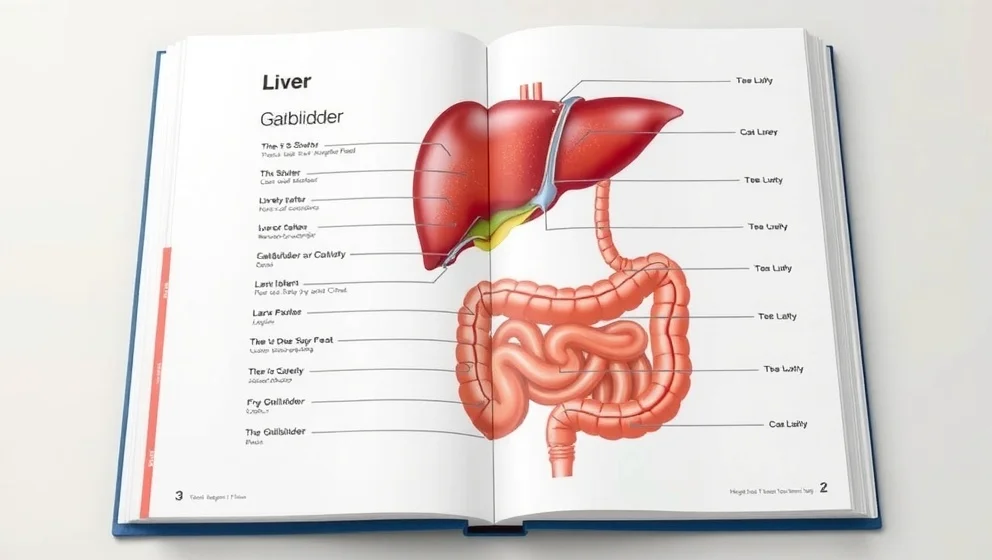

Buken ligger mellan revbenen och bäckenet. Du lär dig var de viktiga organen sitter och hur magen, levern och tarmen fungerar tillsammans.

Gallblåsan sitter gömt under levern på höger sida av magen. Du får veta vad gallblåsan gör och varför den är viktig för matsmältningen.

Levern sitter under höger revben och väger ungefär 1,5 kilo. Den är kroppens största inre organ och gör många viktiga jobb för att hålla dig frisk.